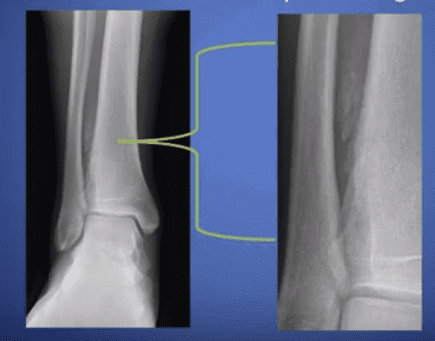

Often used for orthopedic and podiatric use when plain x-rays do not provide the visualization needed, a CBCT (Cone Beam Computed Tomography) scan is a quick, pain-free, noninvasive radiology diagnostic imaging test used to accurately generate comprehensive images of bones. These images can then be reformatted into three-dimensional images which can be easily shared through PACS. Quicker than the spiral motion of a typical CT scan, CBCT imaging exposes patients to less radiation than traditional CT scanners.